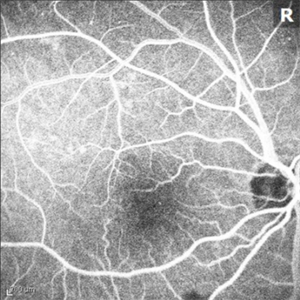

Idiopathic Juxtafoveal Telangiectasia, Type 2

Nov 6 2014 by Thomas A. Ciulla, MD, MBA, FASRS

Note the telangiectactic vessels just temporal to the FAZ.

Photographer: Thomas Steele

Condition/keywords: idiopathic macular telangiectasia, juxtafoveal telangiectasis, parafoveal telangiectasia